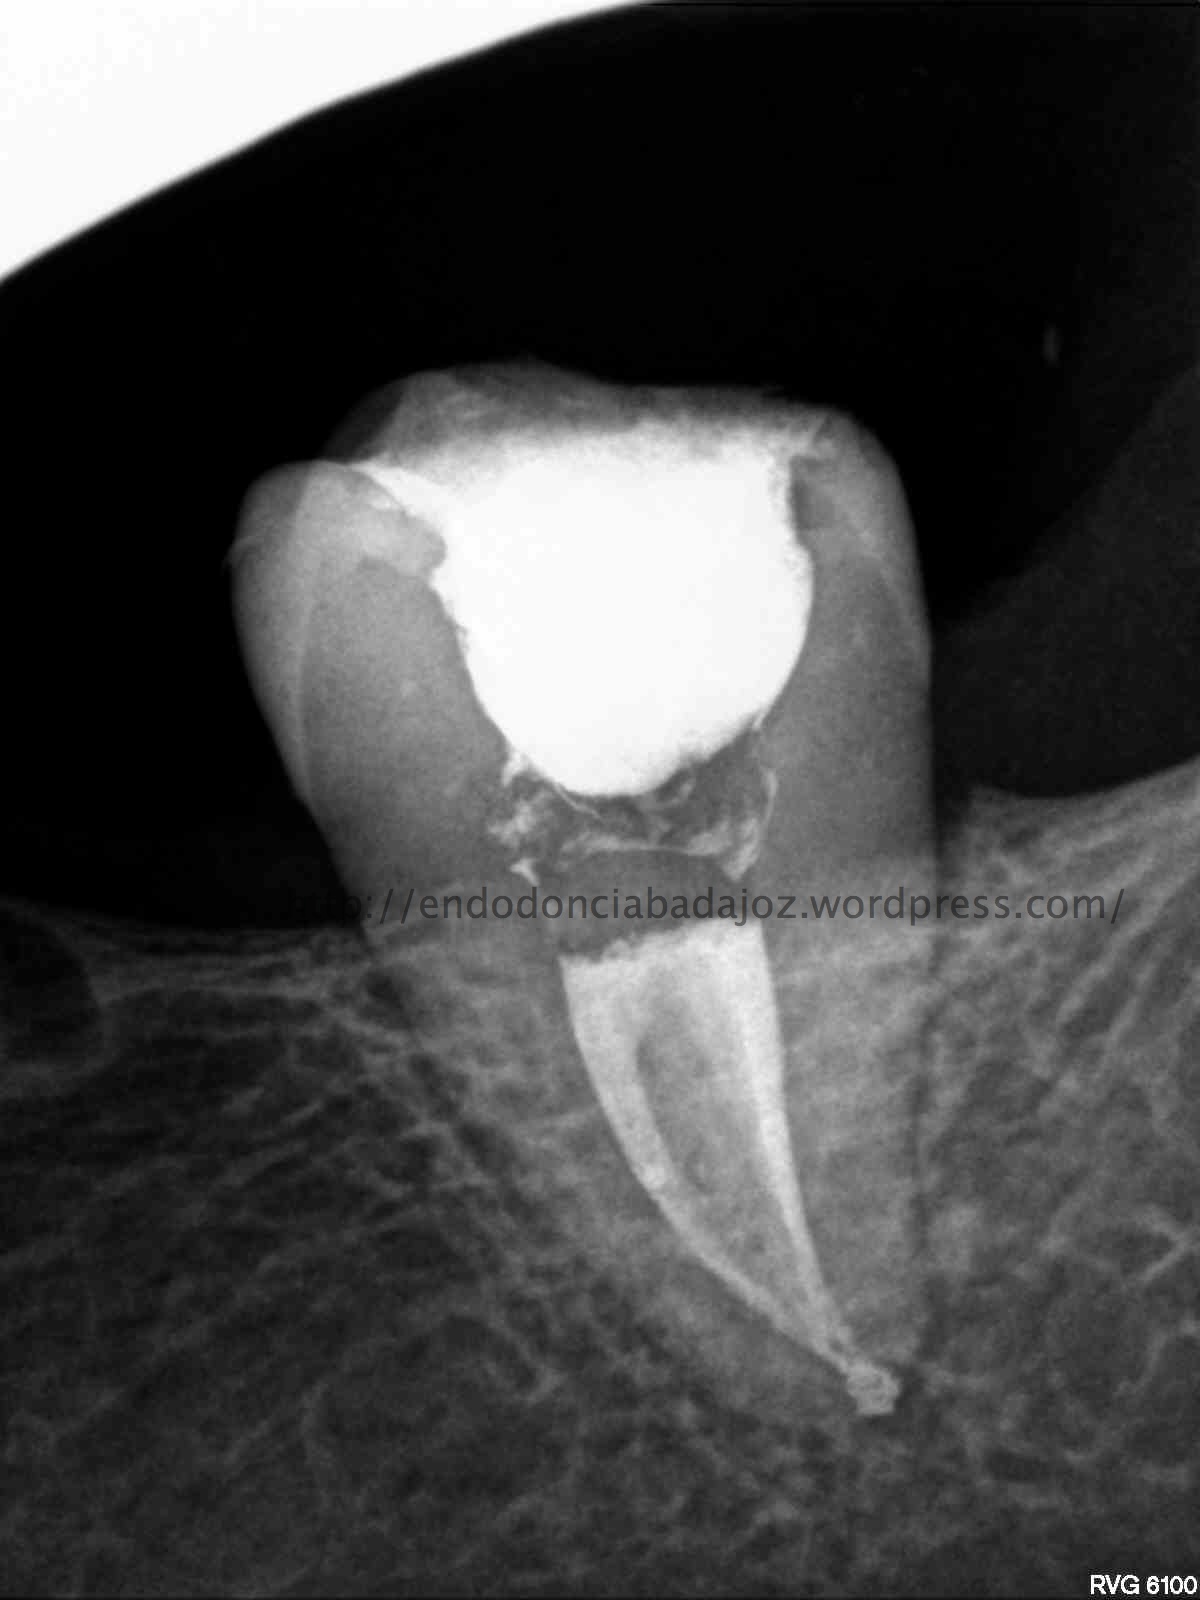

En esta entrada subimos un video de como tratamos un caso que nos mandan , se trata de una pieza 4.6. Tras una exploración radiográfica y la explicación del paciente, que nos refería varios intentos por parte de su odontólogo, sospechamos de una perforación en furca. Con la presencia del M.T.A, este tipo de casos no serán complicadas de tratar y presentan un porcentaje elevado de éxito. Sabemos que depende de la localización, el tamaño y el tiempo que ha transcurrido.

Siento mucho que no publique con una periodicidad determinada, la verdad es que intento publicar casos de interés, esta vez no es más que subir un par de casos de los que me han llegado a revisión el mes de noviembre, para mi, de mucho interés…

Se trata de un par de molares inferiores con lesiones apicales (Periodontitis apicales crónicas ). Consecuencia de caries profundas en su momento.

Se tratan del caso A y el caso B, por orden de posición, ambos casos se instrumentaron de la misma manera, elegimos Protaper hasta una F2, ambos casos se realizaron en una sesión tras abundante irrigación y finalmente se obturaron con condensación Vertical con la técnica de Ola continua de Buchanan complementando en el backfilling con guatpercha inyectada con la Pistola Obtura II.